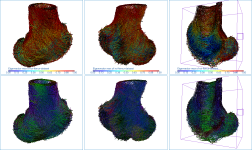

Below are some examples of vector field-based anisotropy maps shown from different aspects. The top row includes visualizations of anisotropy magnitude, while the bottom row shows vector fields colored by orientation. The pair of images on the right show maps that are clipped.

- Maximize the 3D view in the workspace, recommended.

The 3D vector field-based anisotropy map appears in the 3D view at the default settings, with the vectors corresponding to the highest surface anisotropy colored yellow and those corresponding to the lowest, or isotropy, colored blue.

NOTE The Jet LUT is often a good color scheme choice. In this LUT, vectors corresponding to the highest surface anisotropy are colored red, while those corresponding to the lowest, or are isotropic, are colored blue.

- Threshold the vector field-based map to show only high or low anisotropy areas with the Range slider, as shown below.

The thresholded map shown below shows only low anisotropy areas located near articulating surfaces.

- Check the Use direction as color option.

Checking this option will re-code the vector map in accordance with the orientation of the vectors — red for the X axis, green for the Y axis, and blue for the Z axis.

- Apply clipping to evaluate inner surfaces (see Clipping).